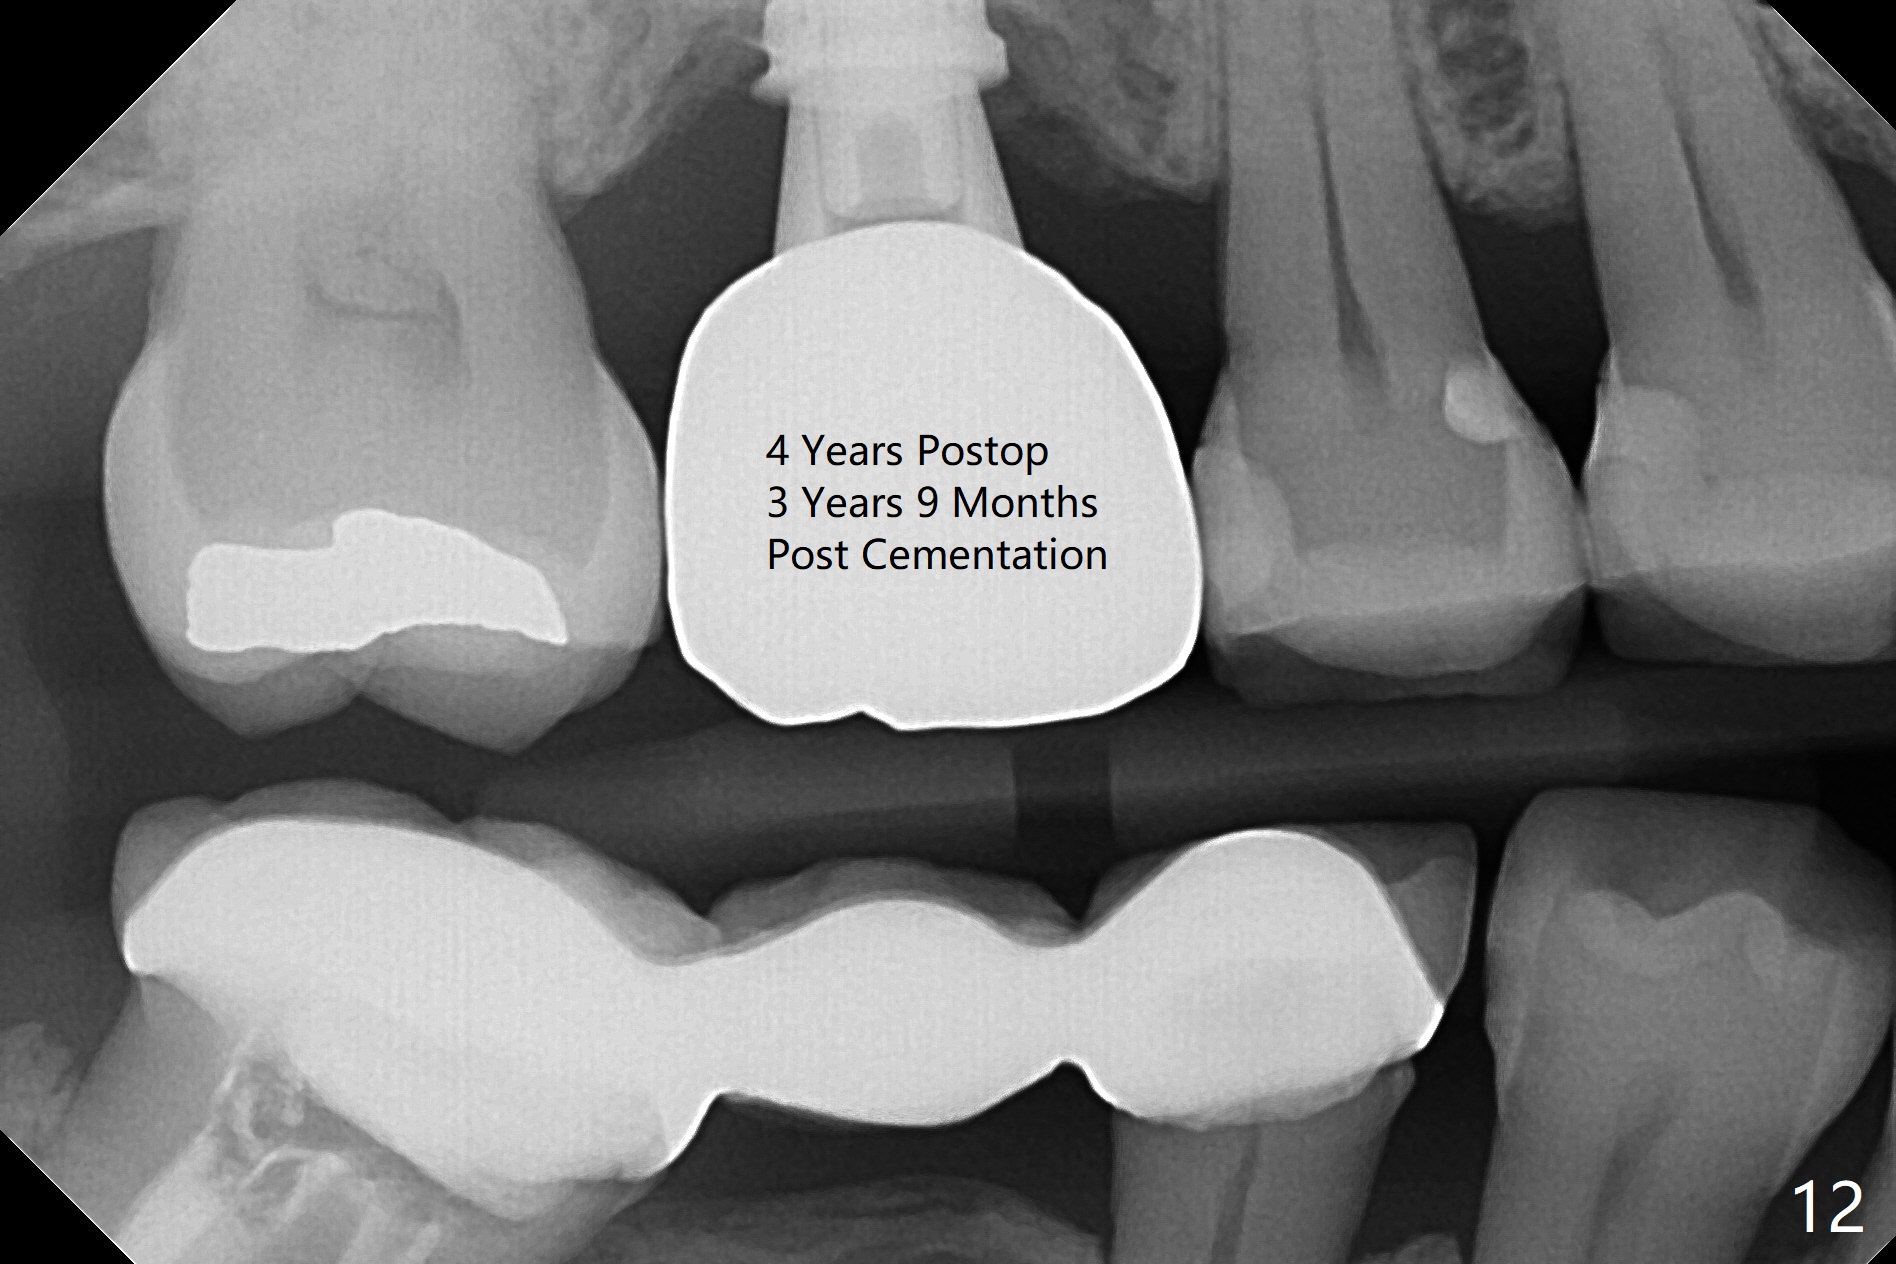

Three weeks postop, the socket has been healing with simultaneous buccal plate collapsing (Fig.5 *, as compared to Fig.2). A larger abutment (7.0-8.5 mm) or a provisional with buccal subgingival margin may decrease the postop shrinking (1,2). There is no bone loss 3 months postop (Fig.6,7). The screw needs to be retightened 9 months post cementation (Fig.8, when the tooth crown is being fabricated at #18). Unilateral mastication is a predisposing factor, since the tooth #19 is missing. When the crown becomes loose again 3 years later, the hex fractures inside the implant. After its removal (Fig.9), a narrower abutment is placed for a new crown (Fig.10: 5x4(4) vs. 6.5x4(4) mm). The implant was placed deep enough without thread exposure; now with apparently complete abutment seating (Fig.11,12). The similar complication may recur due to refusal to have implant at #19 (fear of nerve injury).